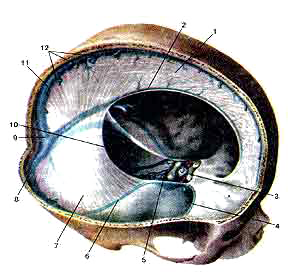

Твердая оболочка головного мозга (dura mater encephali)

Синусы твердой оболочки.

1-серп большого мозга;

2-нижний сагиттальный синус;

3-передний межпешеристый синус;

4-клиновидно-теменной синус;

5-задний межпешеристый синус;

6-верхний каменистый синус;

7-намет мозжечка;

8-поперечный синус;

9-синусный сток;

10-сигмовидный синус;

11-верхний сагиттальный синус;

12-устья верхних мозговых вен.